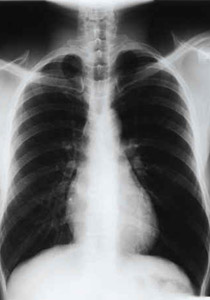

عندما يصاب احد اعضاء الجسم بخلل ما ويضطر الانسان الى زراعة عضو معين من انسان آخر، يتوقع ان العضو "الجديد" سليم، لكن هذا ليس دائما. حيث توفيت امرأة بريطانية في الثامنة والعشرين من عمرها بعد خمسة شهور من عملية زرع رئة لها كانت ملكاً لرجل كان يدخن على مدى 30 عاماً قبل وفاته.

واشتكت عائلة ليندسي سكوت أن الأطباء لم يبلغوها مسبقاً بان من منحها رئته كان يدخن بشراهة. وقد ارسلت الى منزلها بعد عملية جراحية لزرع الرئة على الرغم من أنها ابقيت في غرفة الانعاش لمدة ستة أسابيع. وقالت العائلة ان ليندسي كانت من أشد المتحمسين لمنع التدخين في الأماكن العامة، وعندما طرح الأمر أمام مجلس العموم وشاركت في التظاهرات التي ضغطت على النواب لإقرار الحظر.